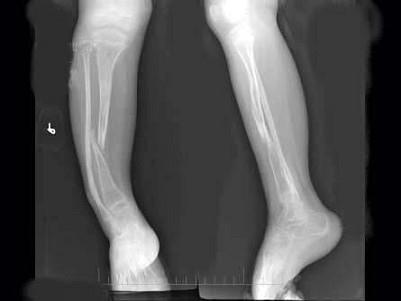

问题 6岁,女,右小腿疼痛,跛行5年,无明显外伤史,右小腿正侧位片如图所示,最可能诊断是?(?)

选项 A.先天性骨不连 B.先天性骨梅毒 C.先天性假关节形成 D.成骨发育不全 E.软骨发育不全

答案 A